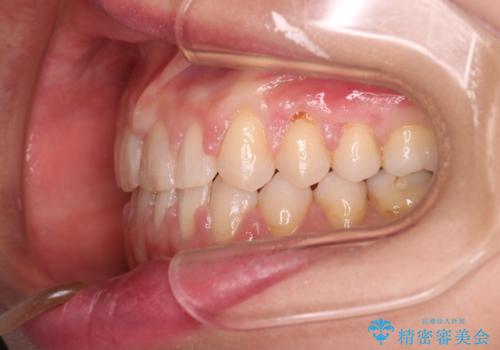

前歯に隙間がいくつかあったため、今回は上下でゴムかけを行いスペースを埋めるための力をかけて閉じました。もう少し早く終了する予定でしたが、ブラッシング不良による歯肉腫脹があり、一部スペースクローズに時間がかかりました。